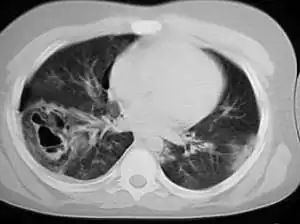

A chest CT scan revealing pulmonary contusions, pneumothorax, and pseudocysts

Computed tomography (CT scanning) is a more sensitive test for pulmonary contusion,[6][33] and it can identify abdominal, chest, or other injuries that accompany the contusion.[38] In one study, chest X-ray detected pulmonary contusions in 16.3% of people with serious blunt trauma, while CT detected them in 31.2% of the same people.[45] Unlike X-ray, CT scanning can detect the contusion almost immediately after the injury.[43] However, in both X-ray and CT a contusion may become more visible over the first 24–48 hours after trauma as bleeding and edema into lung tissues progress.[46] CT scanning also helps determine the size of a contusion, which is useful in determining whether a patient needs mechanical ventilation; a larger volume of contused lung on CT scan is associated with an increased likelihood that ventilation will be needed.[43] CT scans also help differentiate between contusion and pulmonary hematoma, which may be difficult to tell apart otherwise.[47] However, pulmonary contusions that are visible on CT but not chest X-ray are usually not severe enough to affect outcome or treatment.[37]